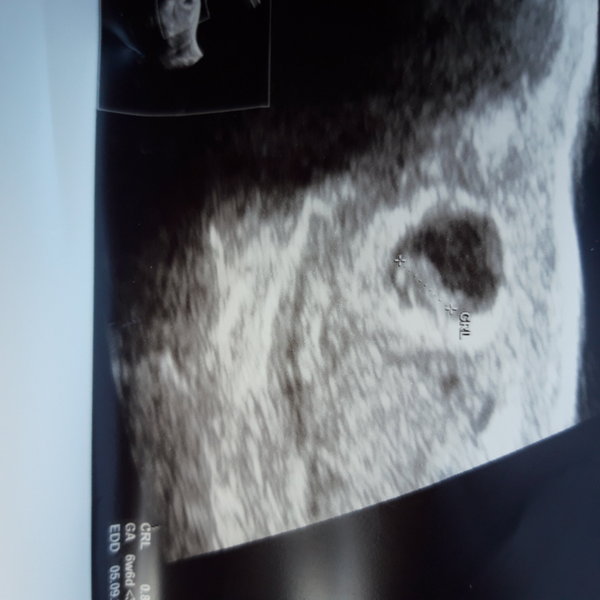

Had a scan today due to previous mmc. We have a heartbeat and measuring ahead off what I thought just by 3 days. Here my little bean

TtcanotherG · 17/01/2020 12:57

I'm not sure why that's gone sideways